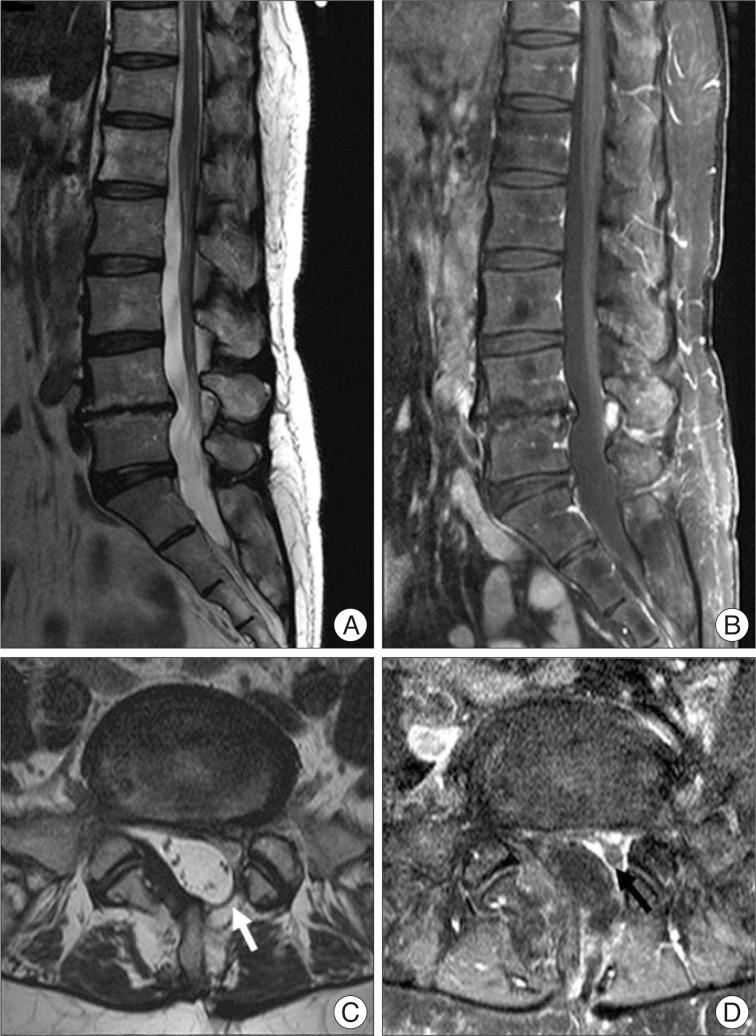

We report a rare complication of iatrogenic spinal intradural following minimally invasive extradural endoscopic procedues in the lumbo-sacral spines. To our knowledge, intradural cyst following epiduroscopy has not been reported in the literature. A 65-year-old woman with back pain related with previous lumbar disc surgery underwent endoscopic epidural neuroplasty and nerve block, but her back pain much aggravated after this procedure. Postoperative magnetic resonance imaging revealed a large intradural cyst from S1-2 to L2-3 displacing the nerve roots anteriorly. On T1 and T2-weighted image, the signal within the cyst had the same intensity as cerebrospinal fluid. The patient underwent partial laminectomy of L5 and intradural exploration, and fenestration of the cystic wall was accomplished. During operation, the communication between the cyst and subarachnoid space was not identified, and the content of the cyst was the same as that of cerebrospinal fluid. Postoperatively, the pain attenuated immediately. Incidental durotomy which occurred during advancing the endoscope through epidural space may be the cause of formation of the intradural cyst. Intrdural cyst should be considered, if a patient complains of new symptoms such as aggravation of back pain after epiduroscopy. Surgical treatment, simple fenestration of the cyst may lead to improved outcome. All the procedures using epiduroscopy should be performed with caution.

我们报告了一例腰骶部微创硬膜外内镜手术后罕见的医源性脊髓硬膜内并发症。据我们所知,文献中尚未报道过硬膜外镜检查后出现硬膜内囊肿的情况。一名65岁女性,因既往腰椎间盘手术相关的背痛接受了内镜下硬膜外神经成形术和神经阻滞,但术后背痛明显加重。术后磁共振成像显示,从S1-2至L2-3有一个巨大的硬膜内囊肿,将神经根向前推移。在T1加权和T2加权图像上,囊肿内信号强度与脑脊液相同。患者接受了L5部分椎板切除术及硬膜内探查,并完成了囊肿壁开窗。手术过程中,未发现囊肿与蛛网膜下腔之间的交通,囊肿内容物与脑脊液相同。术后,疼痛立即减轻。在内镜经硬膜外间隙推进过程中发生的意外硬膜切开可能是硬膜内囊肿形成的原因。如果患者在硬膜外镜检查后出现如背痛加重等新症状,应考虑硬膜内囊肿。手术治疗,单纯囊肿开窗可能会改善预后。所有使用硬膜外镜的操作都应谨慎进行。